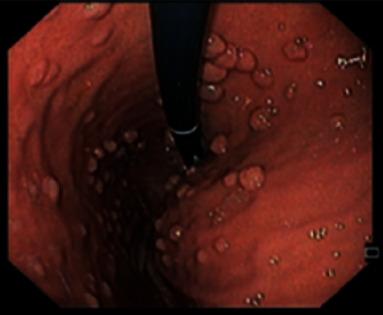

Gardner's syndrome is an autosomal dominant disease caused by a mutation in the gene with 20-30% of cases presenting de novo. This entity is a variant of familial adenomatous polyposis, with a prevalence of 3/100,000 habitants. It may present as early as 2 months of age with a variety of both colonic and extracolonic symptoms. We report a case of a 21-year-old man, without any known family history, presenting with microcytic hypochromic anemia and constitutional symptoms for two months. Ultimately, after the etiological study, Gardner syndrome diagnosis was established as an index primary familiar case. Gardner syndrome is a clinical challenge which requires a prompt suspicion in order to reach its diagnosis. Given the malignant evolution of adenomas in 100% of untreated patients, early identification of extraintestinal manifestations (identifiable prior to colonic symptoms) is of the essence. A consequent endoscopic study to confirm gastrointestinal involvement is essential for a more favorable prognosis.

加德纳综合征是一种常染色体显性疾病,由该基因的突变引起,20%至30%的病例为新发。该病症是家族性腺瘤性息肉病的一种变体,发病率为十万分之三。它最早可在2个月大时出现,伴有多种结肠和结肠外症状。我们报告一例21岁男性病例,无任何已知家族病史,出现小细胞低色素性贫血和全身症状达两个月。最终,经过病因学研究,加德纳综合征被诊断为原发性家族性病例。加德纳综合征是一项临床挑战,需要迅速怀疑以便做出诊断。鉴于100%未经治疗的患者腺瘤会发生恶性演变,早期识别肠外表现(在结肠症状出现之前即可识别)至关重要。因此,进行内镜检查以确认胃肠道受累对于获得更良好的预后至关重要。